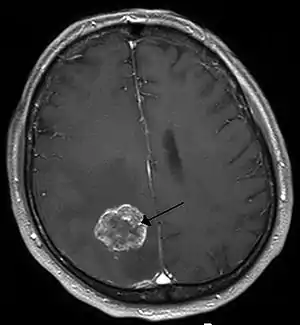

![]() | |

| متاستاز مغز در راست نیمکرههای مغز از سرطان ریه, shown on تصویرسازی تشدید مغناطیسی | |